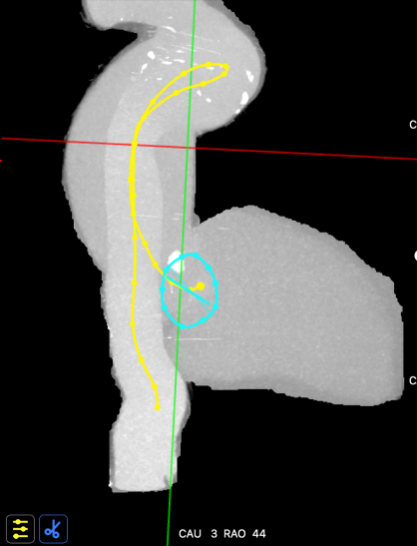

主动脉入路评估

主动脉弓矢状位

主动脉弓冠状位

血管入路三维